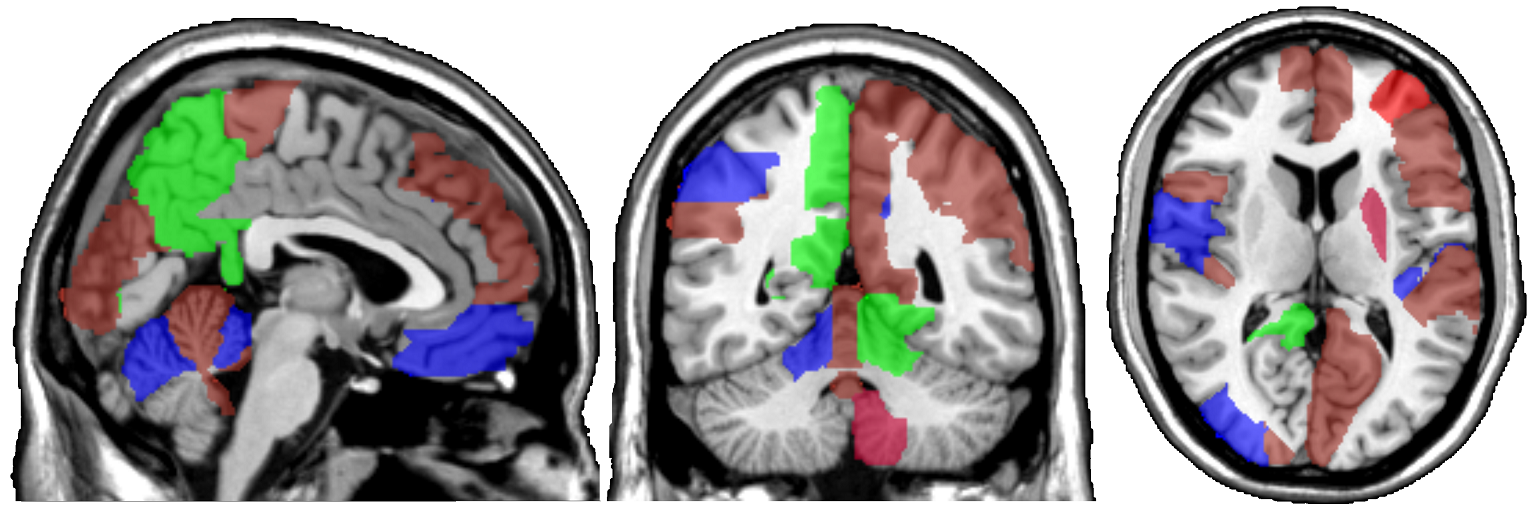

One motivating example for our methods is the application to the functional magnetic resonance imaging (fMRI). The dataset consists of the functional signals of the brain activities measured by blood-oxygen-level-dependent (BOLD), which detects hemodynamic changes based on the metabolic demands followed by neural activities. There are pre-specified regions of the brain, and the BOLD signals associated with multiple voxels in each region are integrated into one signal for that region. Thus, the fMRI data are considered to be multivariate functional data in which each functional predictor represents the signals from a region of the brain. In Section 8, we regress the ADHD index to the regional BOLD activities of the fMRI of the human subjects. There are regions of the brain in the data, and our methods reduce the regions to 41 regions with significantly lower errors than the linear functional regression. Figure 1 displays the regions of the brain’s atlas that are identified by our method. It shows that the methods simplify the data analysis and provide clear representation while keeping the crucial information. The analysis shows that there is an urgent need for new methods in the fields of medical and life sciences as well as other related areas.

In Figure 4 and Figure 5, we display the regions associated with the estimated active sets for IQ and ADHD by the MFG-LASSO respectively. The final active sets of the algorithms were extracted, and matched with the AAL’s atlas where each of the regions has a label. The regions were manually entered into the WFU picked atlas Maldjian and et al. (2003) tool of the SPM-12 ran on MATLAB 2020b to produce mask.nii files. The mask files were imported on MRIcron software to produce the multi-slice images.

The active sets cover the regions associated with IQ in Yoon and et al. (2017) such as cerebello-parietal component and the frontal component. It is mentioned in the paper that the parietal and the frontal regions are strongly associated with intelligence by maintaining a connection with the cerebellum and the temporal regions. The shaded areas cover the ones mentioned in Goriounova and Mansvelder (2019) as well. We provide the name of the regions associated with these active sets in the appendix.

It is interesting that ADHD and IQ have a large proportion of common active sets. For instance, when MFG-LASSO is applied, they overlap in ROIs where the size of active sets are and for IQ and ADHD respectively. On the other hand, the ROIs that are associated with ADHD but not with IQ are the middle and superior frontal, the Parahippocampal, the inferior parietal, and the superior temporal pole gyri. The ratio of the number of right hemisphere regions to the left ones associated with IQ is significantly greater than that of ADHD.